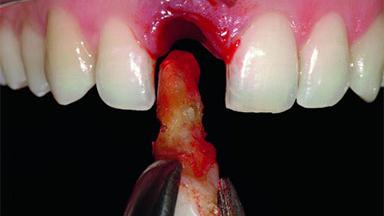

A 32-year-old female Caucasian patient with a compromised maxillary right central incisor was referred to us by a general dentist. Her chief complaints were discomfort and mobility of tooth 11 with unsatisfactory esthetics due to discoloration. The patient reported a previous trauma, some years earlier, as the origin of pathology on the afflicted tooth. Anamnesis was negative for any other dental or periodontal pathology in the remaining dentition. The patient did not take any medication and reported to be a light smoker (5–10 cigs/day). She had high esthetic expectations of her treatment. The extraoral examination revealed a high smile line with full exposure of her maxillary teeth and surrounding soft tissue in the area between the second premolars.

Replacement of an Upper Right Central Incisor with Root Resorption: Ridge Preservation, Delayed Placement of an NC Bone Level Roxolid Implant